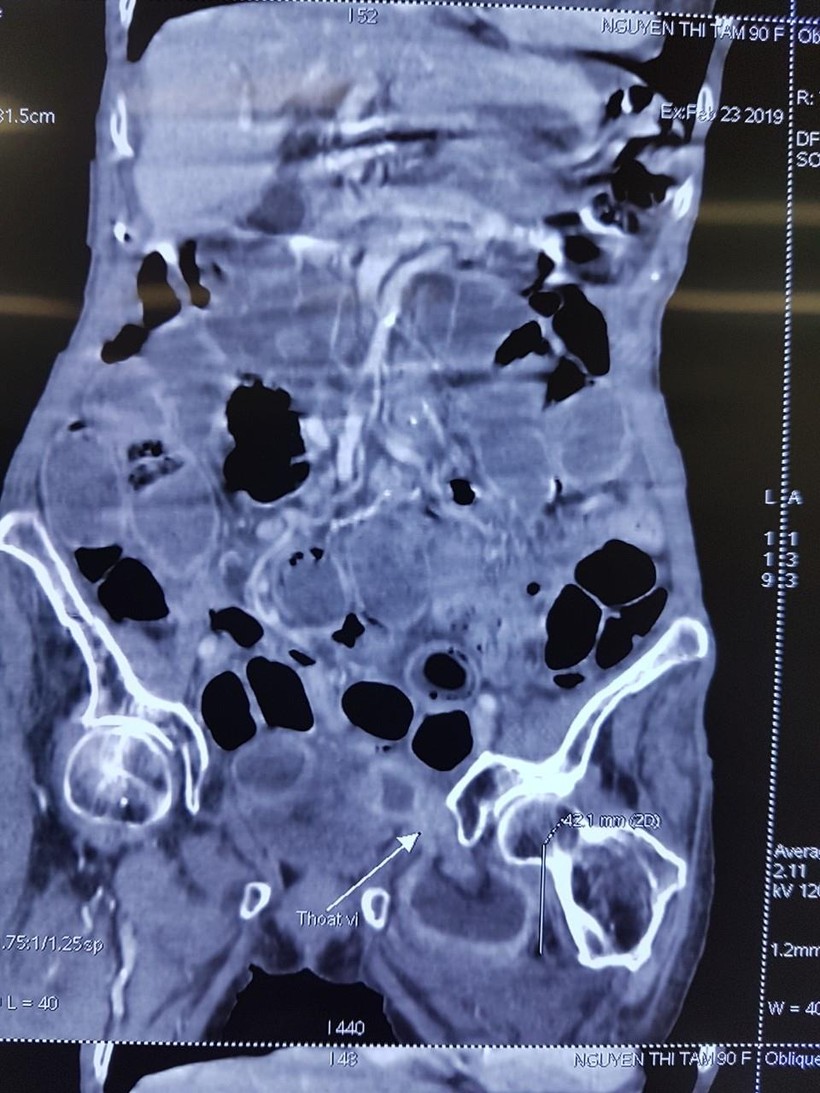

Hình ảnh chụp CT của bệnh nhân

Bệnh nhân lập tức được mổ cấp cứu. Các bác sỹ đã kiểm tra toàn bộ ruột non thấy cách góc hồi manh tràng khoảng 25 – 30cm quai hỗng tràng thoát vị nghẹt vào trong hố bịt. Đúng như chẩn đoán, thành ruột đã bị hoại tử với lỗ thủng có đường kính 2cm, bờ mép nham mở mủn nát, có mủ. Kíp mổ khẩn trương hội chẩn cấp cứu với Chỉ huy Khoa tại bàn mổ ngay trong đêm và quyết định cắt đoạn ruột kèm lỗ thủng, phục hồi lưu thông tiêu hóa. Sau đó, các bác sỹ đã xử lý để tránh tái phát cho bệnh nhân.